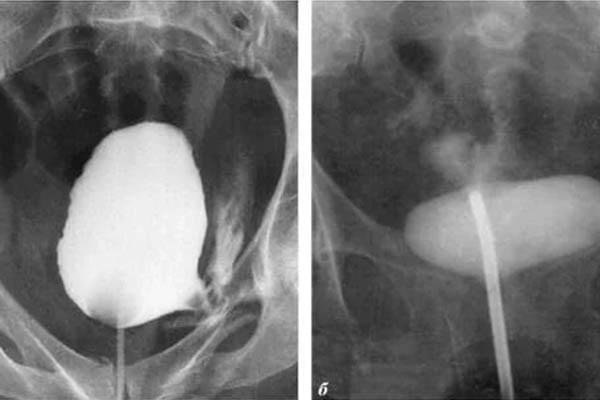

alt_text

Kanker prostat. Ini didiagnosis pada seorang pria berusia 58 tahun. Alasannya adalah penahanan nafsu dalam jangka panjang (dari usia 51). Pria itu meninggal.